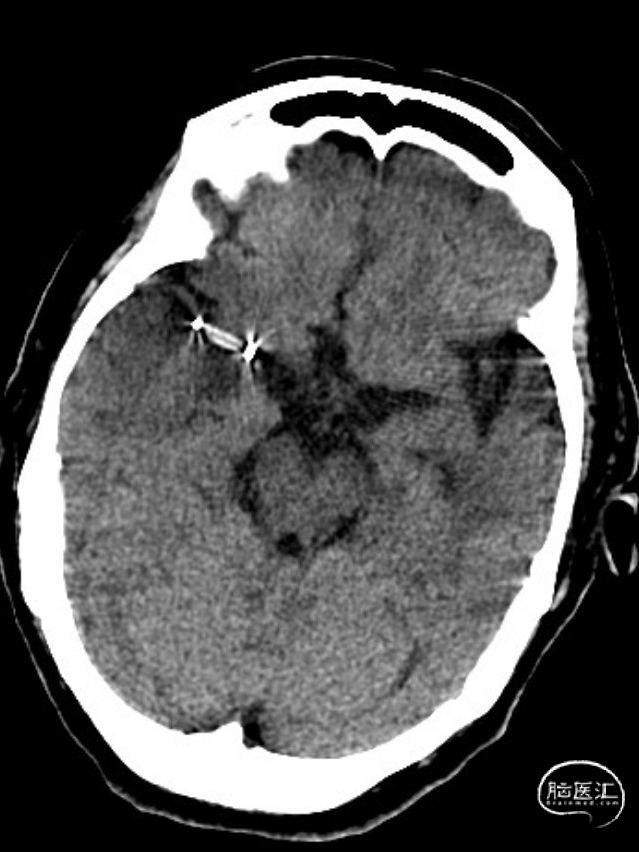

患者为急性脑梗死,头颅CT未见明显低密度病灶,CTA提示:右侧颈内动脉及右侧大脑中动脉M1段闭塞,远端分支减少,显影浅淡。目前患者神经功能缺损严重,有急诊取栓手术指征。

造影显示RICA:C1段起始部闭塞,残端呈锥形,TICI分级0级;RMCA未显影,远端由RACA经皮层支少量代偿,ASITN分级1-2级。

术后第一天复查颅脑CT未见异常染色及大面低密度病灶。